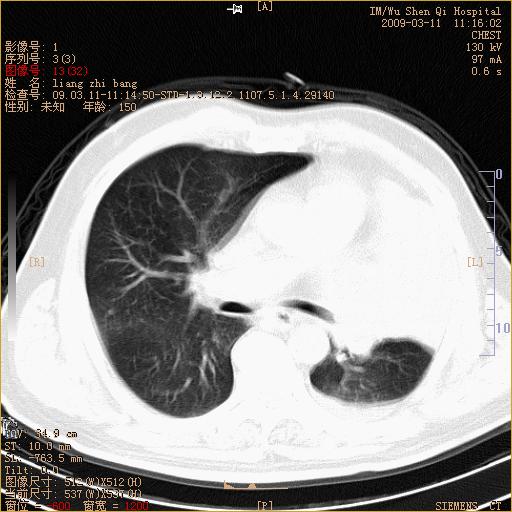

标题: CT18604:男,60岁,咳嗽一月余 [打印本页]

标题: CT18604:男,60岁,咳嗽一月余

1)考虑左肺上叶中央型肺癌并左肺上叶肺不张;建议必要时行纤支镜检查进一步明确诊断。2)左侧胸腔积液。

肺门肿块、支气管开口闭塞伴肺不张及胸水!典型的中心型肺癌变现!

1、左肺上叶中央型肺癌并上叶阻塞性肺不张。

2、左侧胸腔少量积液,右侧胸膜轻度增厚。

左肺们肿块并左肺上叶不张。考虑左肺中心性肺癌并左肺上叶不张及左侧胸腔积液